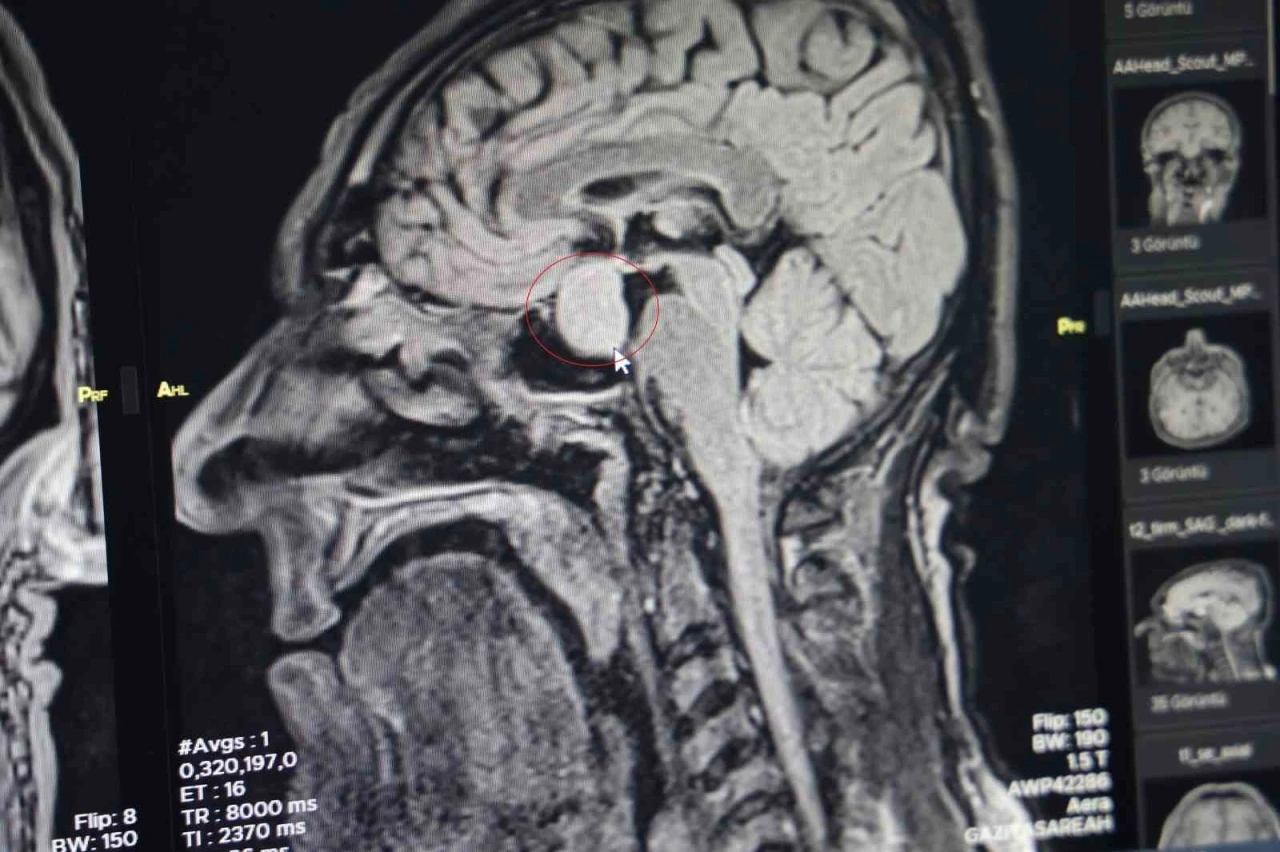

Hastanın başvurusu, burun kökü ve dilinde kabalaşma, ses kalınlığı gibi şikayetlerle oldu. Yapılan tetkikler sonucunda, dış merkezlerde çekilen MR’larda hipofiz bölgesinde bir iyi huylu tümör tespit edildi. Bu nedenle hasta, hastaneye başvurdu. Beyin Cerrahi Bölümü’nde yapılan tetkiklerin ardından, hastanın büyüme hormonlarının yüksek olduğu belirlendi ve kapalı yöntemle hipofiz tümörü başarıyla alındı.

Doç. Dr. Abdurrahman Çetin, hastayı ameliyat öncesinde bilgilendirdiklerini ve operasyonun çok başarılı geçtiğini belirtti. "Hastanemizde ilk defa burundan kapalı yöntemle girilerek hipofiz tümörüne müdahale ettik. Allah’a şükür, sağ salim bir şekilde tümörü aldık. Operasyonumuz 2-2,5 saat sürdü ve herhangi bir komplikasyon gelişmeden başarılı bir şekilde tamamladık" diyerek, hastanın hızlı bir şekilde iyileştiğini belirtti. İki gün sonra hastanın taburcu edilmesi sağlandı.